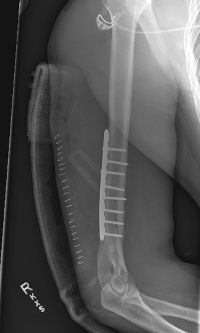

Surgical Repair of Fracture With Plate and Screws